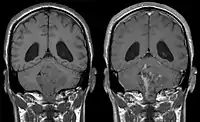

- Ependymoma of 4.ventricle in MRI.

- Ependymoma of 4.ventricle in MRI. Left without, right with contrast-enhancement.